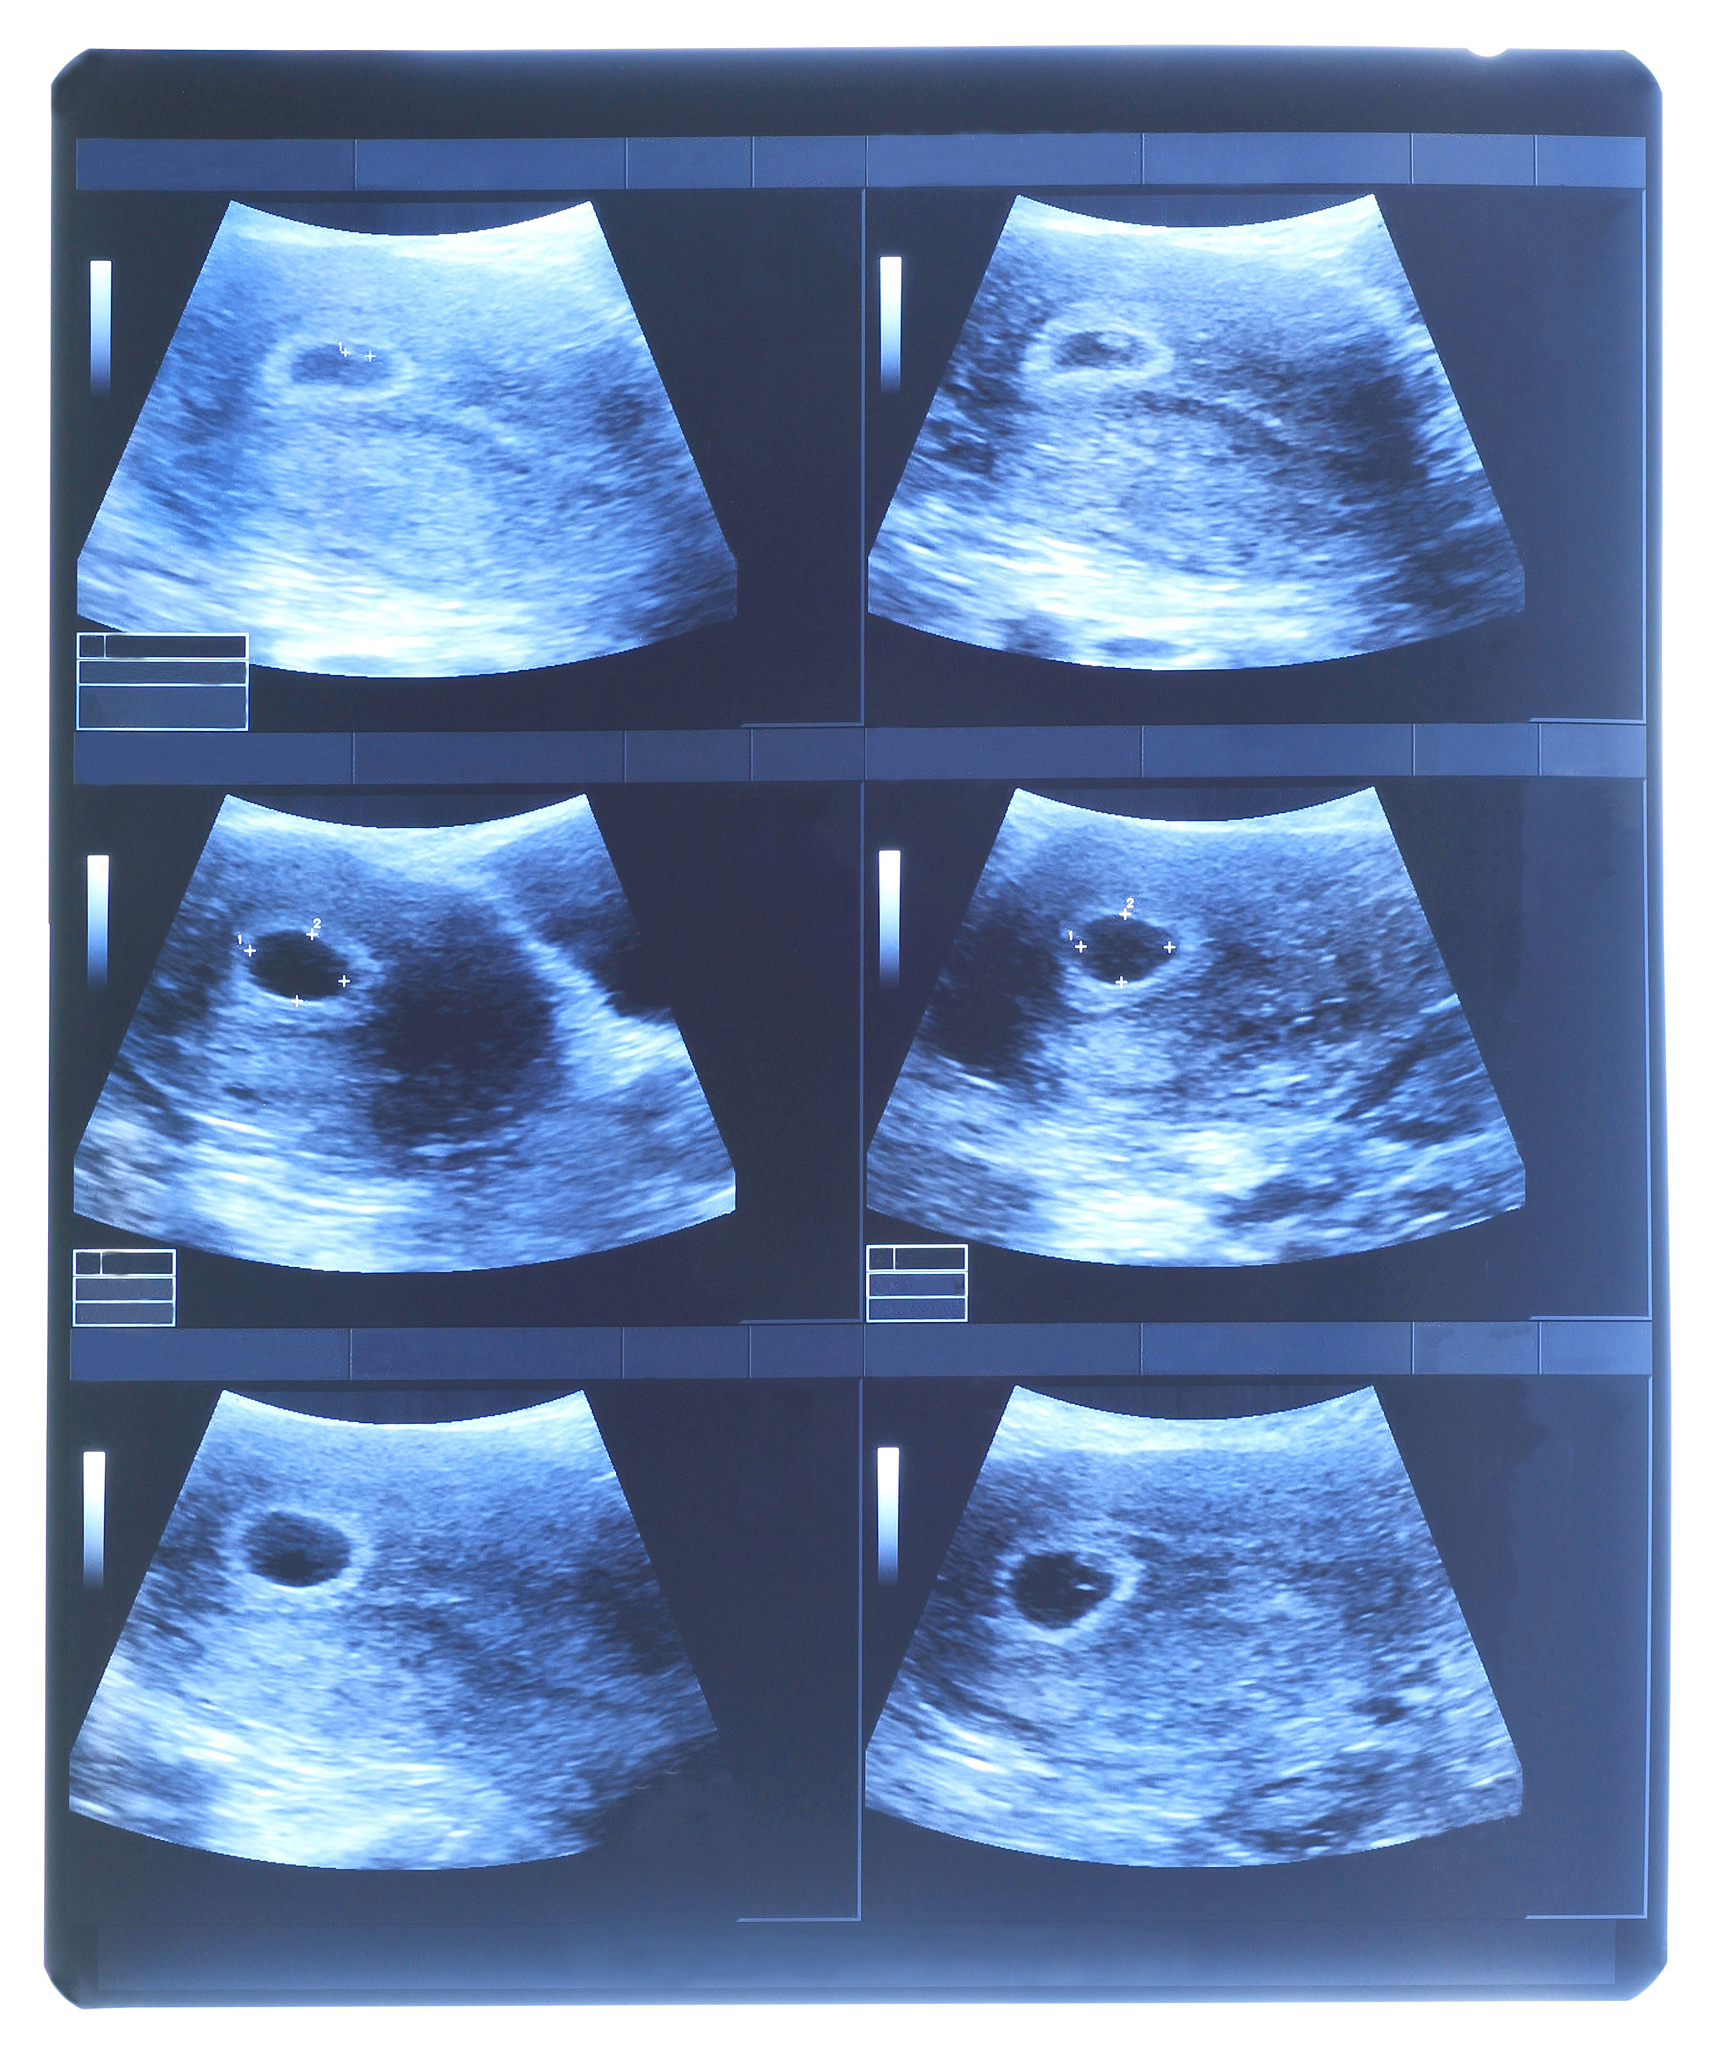

宫腔粘连是一种常见的妇科疾病,严重影响女性生育能力。近年来,中西医结合治疗宫腔粘连取得了显著进展,其中脐带间充质干细胞 (MSCs) 的应用备受关注。MSCs 具有多向分化潜能和免疫调节作用,可以有效修复受损的子宫内膜,改善宫腔环境。

研究表明,CXCR4 和 TGF-β 在宫腔粘连的发生发展中起重要作用。CXCR4 是一种趋化因子受体,TGF-β 是一种重要的细胞因子,两者均参与子宫内膜的修复和再生。MSCs 通过分泌多种细胞因子和生长因子,调控 CXCR4 和 TGF-β 的表达,促进子宫内膜的修复,抑制粘连的形成。